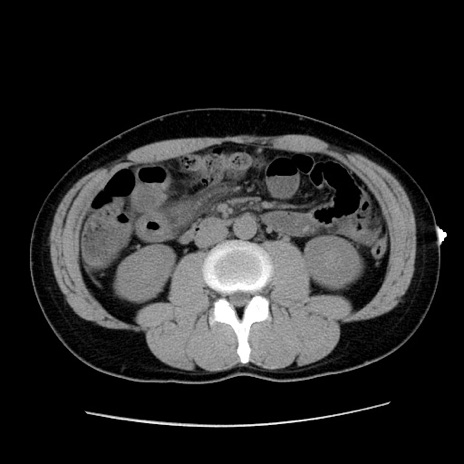

症例36(横断像)

【症例】20歳代 男性

【主訴】心窩部痛

【現病歴】今朝より上腹部痛あり。一旦軽快していたが再度出現したため救急要請。昨日夕に白身の魚を含む刺身を食べた。

【身体所見】BP 136/89mmHg、HR 74/min、BT 37.0℃、腹部:膨満、軟、心窩部に圧痛あり。反跳痛なし、筋性防御なし、腸雑音やや亢進あり。

【データ】WBC 17700、CRP 0.48